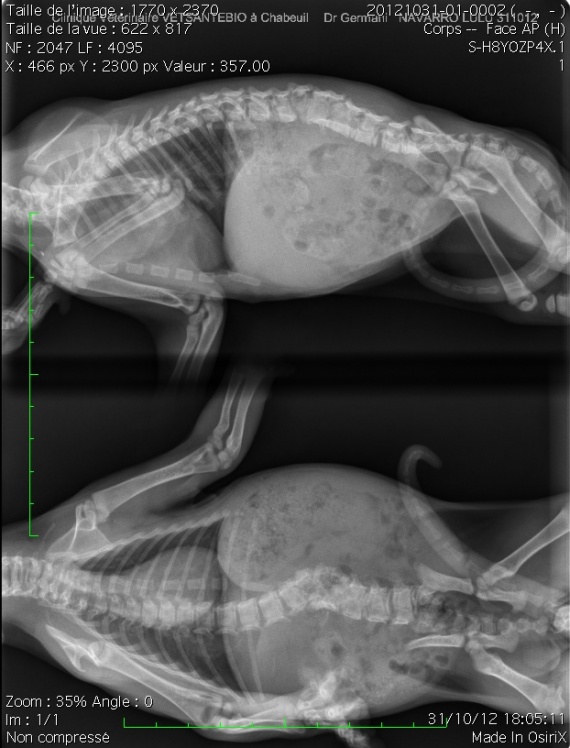

Libérer le Diaphragme #2 Détendre le muscle Psoas en position couchée Libérer le Diaphragme #3 Détendre les muscles inter omoplates Libérer le Diaphragme #4 Mobilisation Bonjour à Tous, Ci joint la radio de notre petite Lulu, chaton née le 17 Septembre 12 Quand nous l'avons eu, il était Ce dernier est dû à la présence d'un grand nombre de vaisseaux sanguins et lymphatiques dans les tissus pulmonaires Selon les résultats de l'autopsie, le cancer du poumon